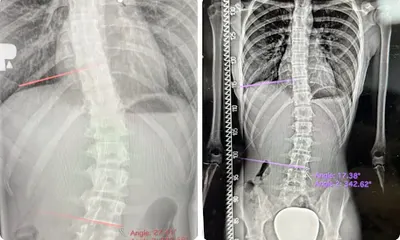

### Gabinet ortopedyczny Hagart Waldemar Podkoń w Skierniewicach W Skierniewicach, przy ulicy Rawskiej 54 (kod pocztowy 96-100), prowadzi działalność gabinet ortopedyczny Hagart Waldemar Podkoń. Specjalista ten zajmuje się leczeniem schorzeń układu ruchu, w tym problemami kręgosłupa i innymi dolegliwościami ortopedycznymi. Lokalizacja w centrum miasta ułatwia dostęp pacjentom z regionu, a gabinet wpisuje się w lokalną ofertę usług medycznych dla mieszkańców Skierniewic i okolic. Na platformie Google gabinet Hagart Waldemar Podkoń otrzymuje ocenę 2,0 na 5 gwiazdek na podstawie 5 opinii. Klienci dzielą się mieszanymi doświadczeniami: jedna osoba chwali lekarza za uprzejmość i miłe podejście, polecając wizytę. Z drugiej strony, kilka negatywnych komentarzy wskazuje na brak empatii i profesjonalizmu. Pacjenci skarżą się na obraźliwe traktowanie, w tym wulgarne zwroty i nieodpowiednie komentarze w sytuacjach bólowych, co budzi poważne zastrzeżenia. Jedna z opinii wspomina o zgłoszeniu sprawy do organów nadzoru. Potencjalni pacjenci mogą sprawdzić aktualne informacje o dostępności bezpośrednio w gabinecie. W dobie rosnącego zapotrzebowania na opiekę ortopedyczną, opinie te warto uwzględnić przy wyborze specjalisty w Skierniewicach. (Słowa: 198)

Centrum Chorób Kręgosłupa Łukasz Stoliński